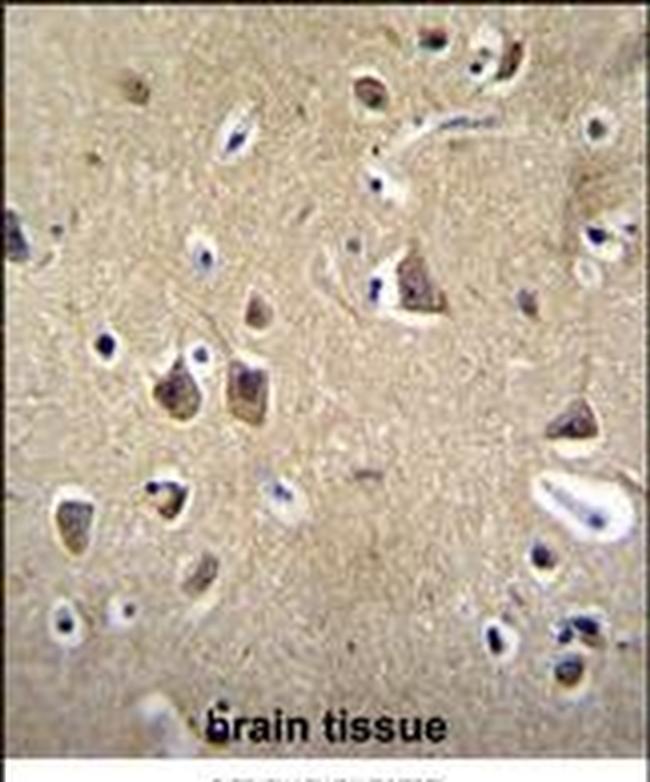

- Immunohistochemical analysis of FADS6 in paraffin-embedded human brain tissue. Samples were incubated with FADS6 polyclonal antibody (Product # PA5-71542) followed by a peroxidase-conjugate secondary antibody and DAB staining.